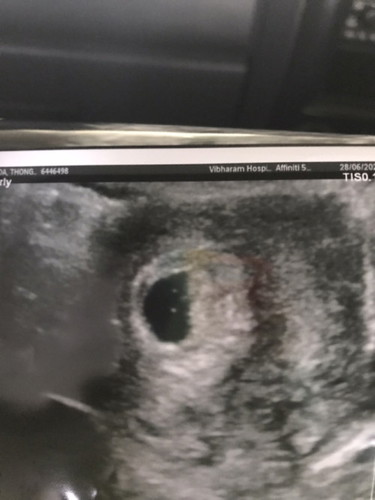

5w อัลตร้าซาวล์ยังไม่เจออะไรแบบนี้ปกติไหมคะ กังวลมากค่ะ หมอนัดดูอีก2สัปดาห์

ปกติจ้า ของเราตอน5w1dก็ไม่เจอค่ะ ซาวล์ทางช่องคลอดนะเจอแต่ถุงตั้งครรภ์กับถุงไข่แดงหมอนัดอีกวันที่12นี้เดียวก็เจอน้องค้าาา😊

ปกติค่ะ เราเจอน้องมาพร้อมกับหัวใจตอน6วีคค่ะ คุณแม่รออีก1-2วีคนะคะ คุณหมอบอกว่าบางคนก็เจอตอน8วีคเลย

เราก็เป็นคะ อายุครรภ์ยังน้อย ยังอาจไม่เจอน้อง เราเจอน้องตอน 8 สัปดาห์ จ้า

อัพเดทค่ะ 7w 6d เจอต้าวก้อนแล้วค่า ขอบคุณแม่ๆมากเลยค่า

อัพเดท 7w5d เจอต้าวก้อนแล้วค่าแม่ๆ